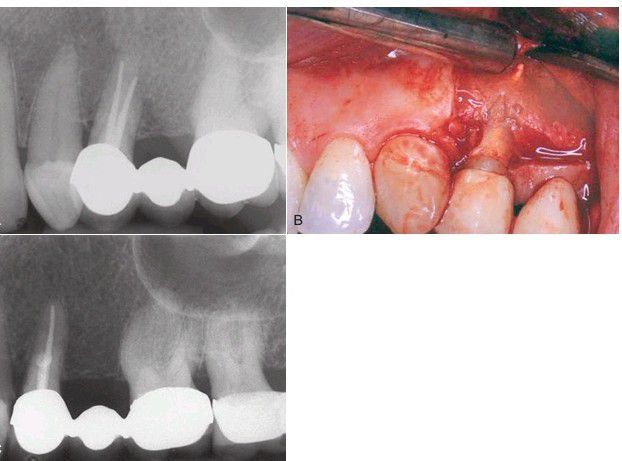

. (A) The patient had persistent pain over the midroot region following what appears to be successful endodontic treatment. (B) Surgical exploration reveals perforation of the buccal root during the endodontic treatment with displaced gutta-percha. (C) Postoperative periapical film of surgical removal of the extruded gutta-percha and mineral trioxide aggregate seal.